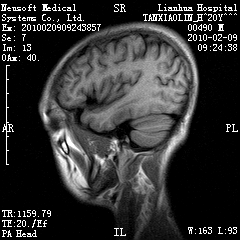

20岁男性患者,平时偶有头痛而无其他不适,现因持续头痛服药后无缓解而来院就诊。

松果体囊肿?

松果体区占位继发轻度脑积水?该患者有ct资料,我已发上。

考虑松果体囊肿。